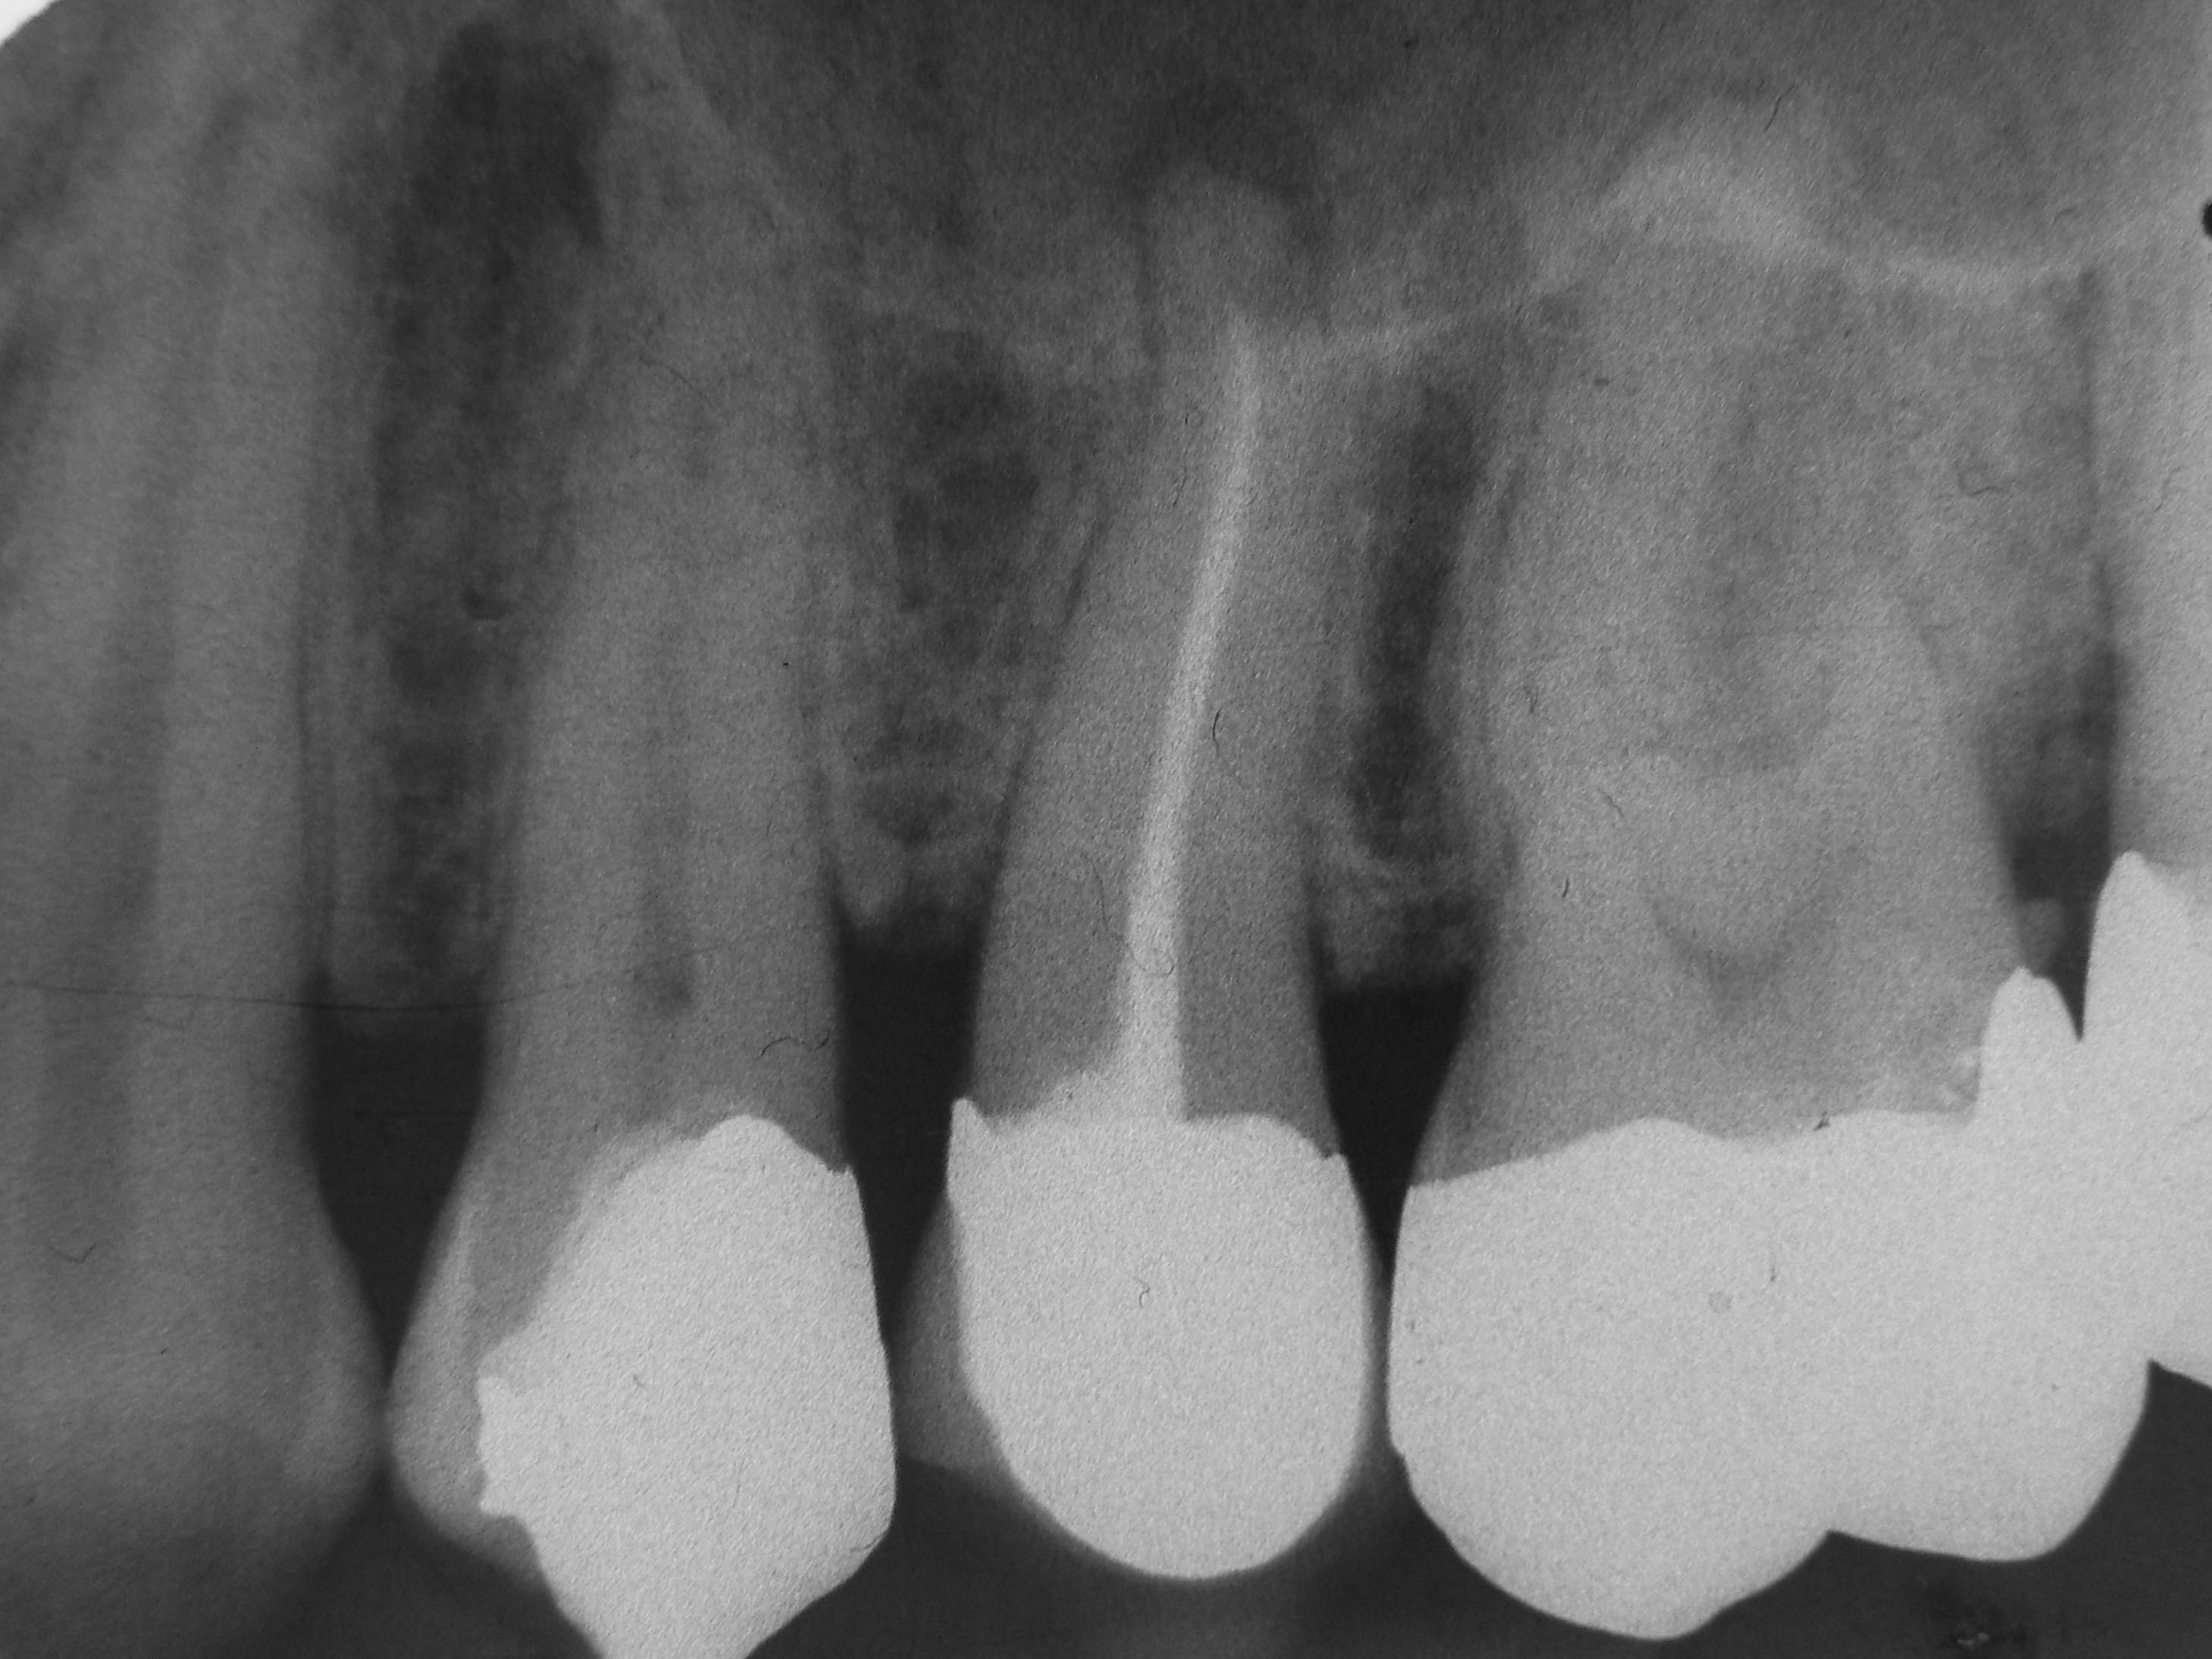

24 25 prätherapeutische Rö 2000 Veröffentlicht 4. November 2013 am 2918 × 2189 in „Chapeau“ oder der Wirt und die Wette 24 25 prätherapeutische Rö